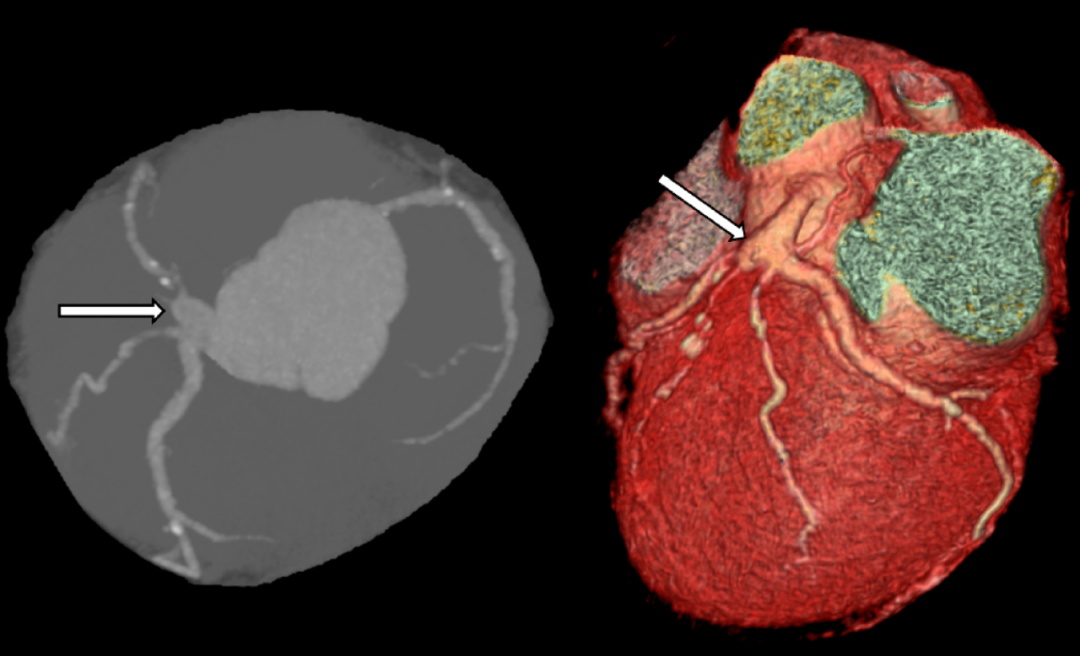

图5、CT中左冠状动脉主干的动脉瘤样病变(箭头)

冠状动脉CT血管成像(CCTA)

核心优势:准确评估动脉瘤大小、位置、钙化及血栓负荷,可三维重建血管解剖,指导外科手术规划(如左主干动脉瘤与周围结构关系)。

推荐场景:无症状人群筛查、已知CAAE患者的长期随访。